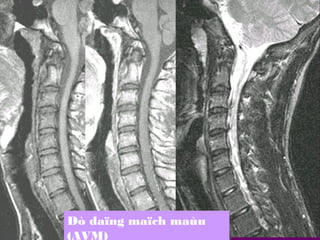

+Toån thöông maïch maùu:

daäp tuyû, daäp-xuaát huyeát,

AVM

Dò daïng maïch maùu

(AVM)